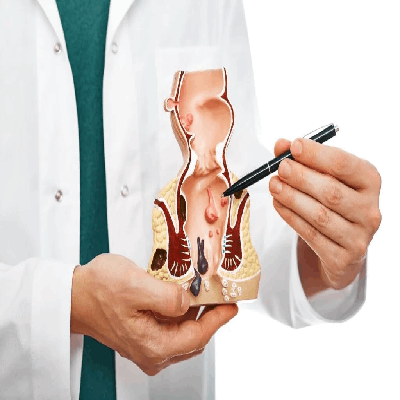

Piles Care

Piles Care